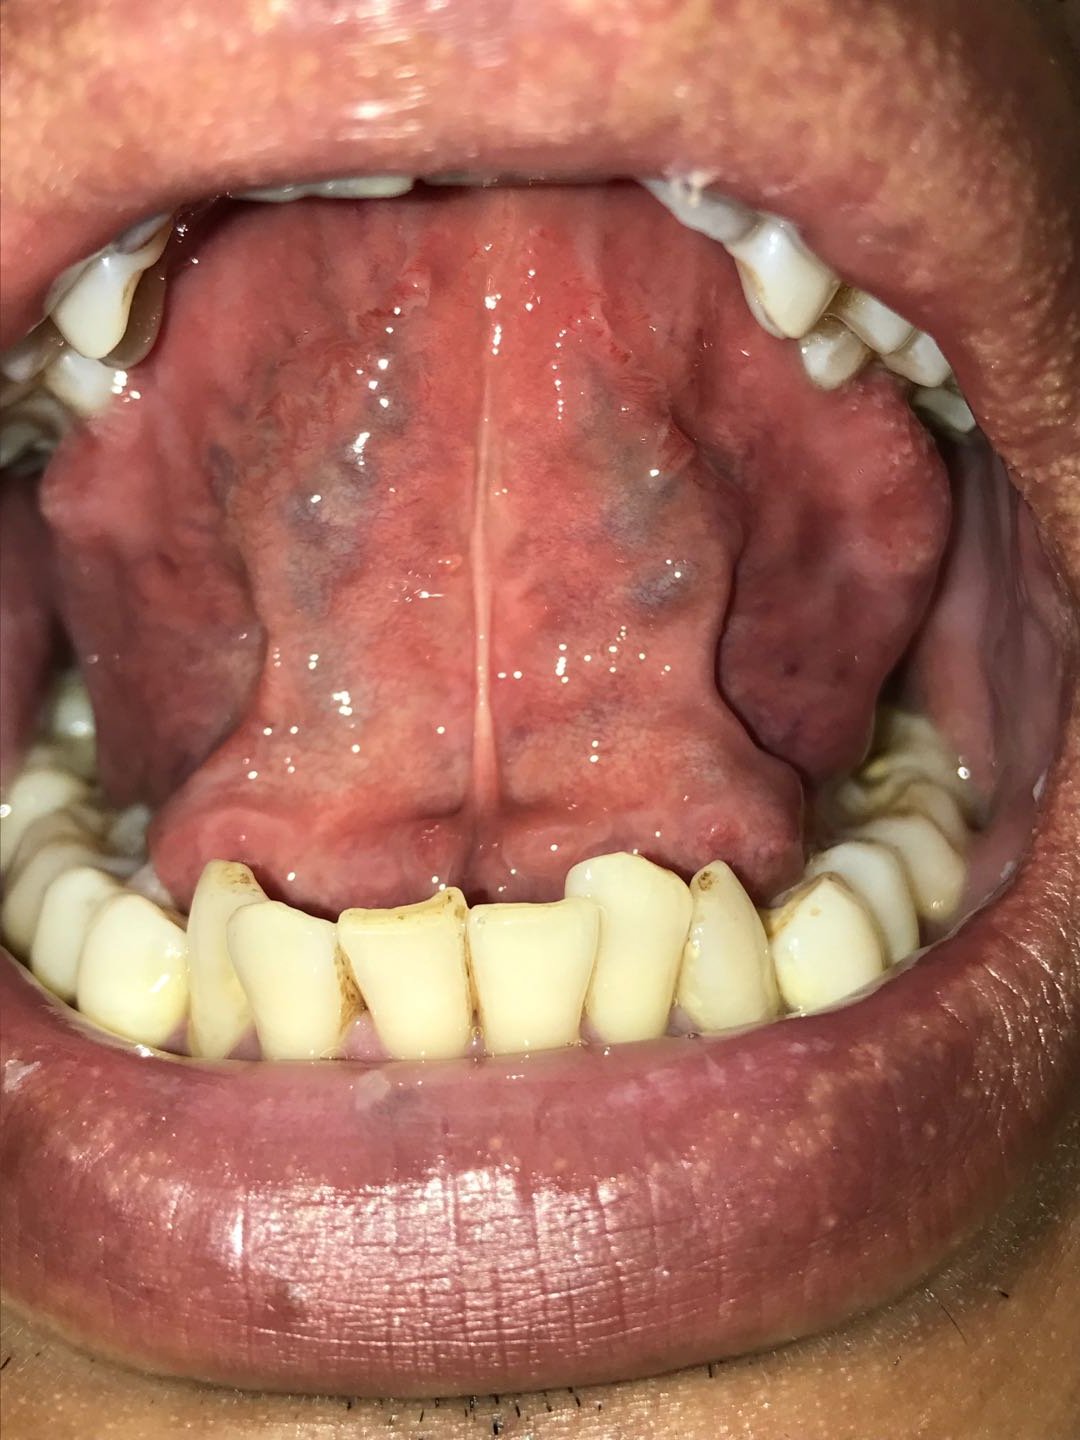

1、舌苔黄厚,如下图所示;